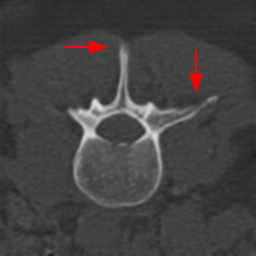

Disentanglement and explicit shape constraints. As shown in Fig. 4, we can see streak metal artifacts nearly everywhere in . M1 can roughly disentangle artifacts and anatomical information but strong vertical artifacts and strange air area appear in (see red arrows of M1 in Fig. 4). For the anatomical structure, M1 learns to segment vertebrae with fully supervised and applied on various CT images, but fails to suppress the false bony structure in and as may misclassify some metal artifacts as bone.

Implicit shape constraints. With , all segmentations are improved with higher Dices and smaller ASDs, see Table 1. As shown in Fig. 4, , and become similar but the high density bone is not correctly segmented in as it maybe treated as metal artifacts. Comparing between M2 and M1, the abnormal air region disappears but metal artifact reduction performance is still not satisfactory.

Anatomy-aware generation. With AADE layer in M3, , and are substantially improved as shown in Table 1. Note, is used as attention map, so we do not expect it to be identical to . In , metal artifacts are further suppressed comparing with M2. Thus, AADE is critical to our anatomy-aware artifact disentanglement framework. With the special structure, can be punished in the image translation and reconstruction processes and the other encoders and generators receive more guidance. However, as shown by blue arrows in Fig. 4, we observe a shadow of vertebra edge of appears in of M3 and the vertebra boundaries get smoothed out in . It may be because sharp edges are encoded as metal artifacts and forced to be added to by artifact consistency loss .

Removal of . To mitigate vertebrae shadows, we remove . The segmentation performance of most images in M4 gets improved because of better synthetic images. Overall, in M4 yields the best segmentation performance for CBCT images with an average Dice of 0.847 and an average ASD of 1.54 mm. For the synthetic images, M4 generates with the best quality and least metal artifacts among all the models. M4 also outputs without vertebra shadows. The results indicate our shape-aware network could preserve anatomical details and transfer the metal artifacts precisely without .

2D segmentation. Our model is compared with two methods based on domain adaptation: AdaptSegNet [16] and SIFA [2]. AdaptSegNet and SIFA are trained with the officially released codes. AdaptSegNet is trained with Dice loss as we only have one class here. The results are summarized in Fig. 6 and Table 2(a). AdaptSegNet invokes DeeplabV2 as the segmentor and cannot capture the vertebra especially when metal artifacts exist. SIFA outputs plausible predictions but the performance is heavily affected by the metal artifacts. Also, the segmentations predicted by SIFA can not capture vertebrae precisely and show false positive bones and enlarged masks (see red arrows in Fig. 6). With joint learning, our model achieves the best segmentation performance with an average Dice of 0.847 and an average ASD of 1.54mm.

Modality translation and artifact reduction. Here we compare our model with other methods: CycleGAN [21], DRIT [8], ADN [9]. All the models are trained with our data using their officially released codes. Further, we train a UNet segmentation network using annotated CT data and apply it to synthesized CT images as an anatomy-invariant segmentation evaluator. As shown in Table 2(b), our model achieves the best performance with a much larger average Dice compared with other methods. Fig. 6 shows the synthetic images and segmentation results. CycleGAN and DRIT tend to output plausible and realistic CT images but are not able to preserve the anatomical information precisely. As shown by the red arrows in Fig. 6, the bony structures appear distorted and noisy. ADN can retain most of the anatomical information but not for the bone pixels with high intensity, which might be classified into metal artifacts. With anatomical knowledge learned from the CT domain, our model outputs high-quality synthetic CT images while keeping anatomical consistency.

For artifact reduction, ADN and DRIT [8] could not successfully recover the clean images and streak artifacts remain in the synthetic image (see blue arrows in Fig. 6). CycleGAN [21] could output clean images but the distorted bones make them less valuable. Our model can suppress all the artifacts and keep the bone edges sharp, which outperforms all the other methods.